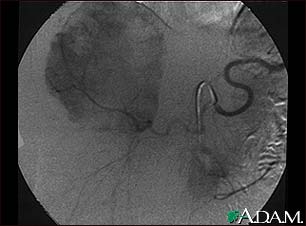

Hemangioma - angiogram

This angiogram (an X-ray taken after dye has been injected into the blood stream) shows a mass of blood vessels (hemangioma) in the liver.